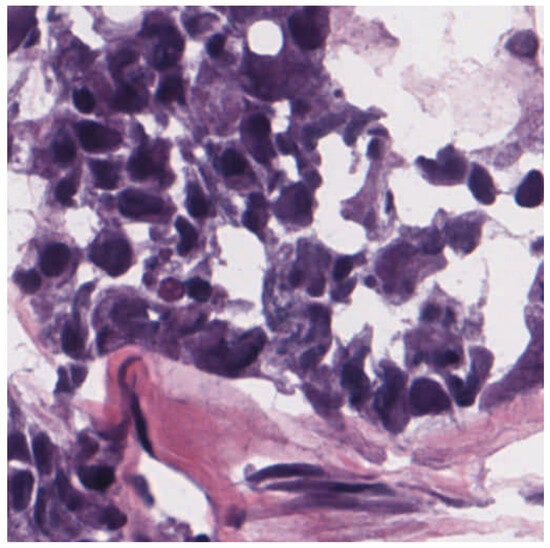

3.3. Dermatopathology

- Olsen, T.G.; Jackson, B.H.; Feeser, T.A.; Kent, M.N.; Moad, J.C.; Krishnamurthy, S.; Lunsford, D.D.; Soans, R.E. Diagnostic Performance of Deep Learning Algorithms Applied to Three Common Diagnoses in Dermatopathology. J. Pathol. Inform. 2018, 9, 32. [Google Scholar] [CrossRef]

- Zhang, J.; Zhang, X.; Qu, D.; Xue, Y.; Bi, X.; Chen, Z. A Deep Learning Approach for Basal Cell Carcinomas and Bowen’s Disease Recognition in Dermatopathology Image. J. Biomater. Tissue Eng. 2022, 12, 879–887. [Google Scholar] [CrossRef]